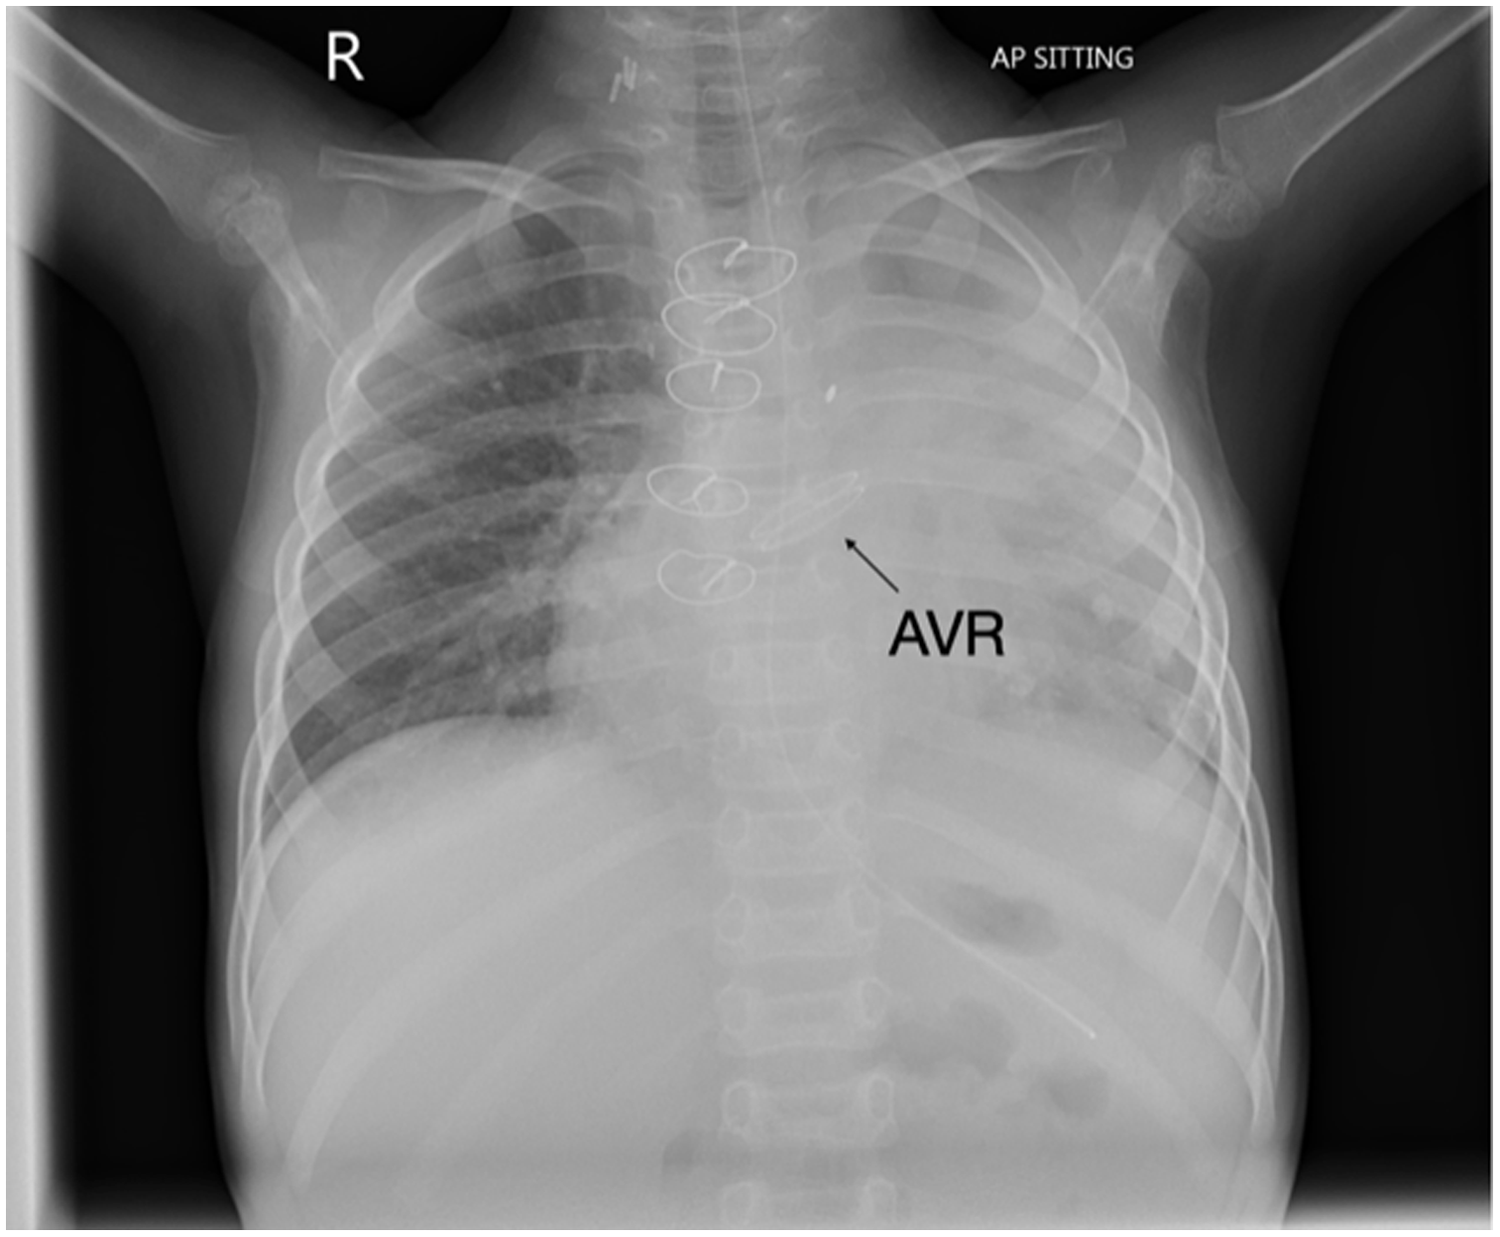

She had a difficult post-transplant course and suffered several complications including malabsorption requiring nasogastric and then nasojejunal feeding, liver dysfunction, thoracolumbar osteoporotic wedging and compression fractures (treated with vitamin D), renal impairment with echogenic kidneys and adrenocortical insufficiency. She also developed several episodes of sepsis including Epstein–Barr viraemia, Burkholderia cepacia, Stenotrophomonas maltroplilia, Klebsiella oxytoca and Pseudomona aureginosa sepsis requiring several antibiotics including ceftolazone-tazobactem, micafungin and aztreonam with taurolidine nebulizers. She developed a pulmonary haemorrhage soon after her transplant and needed tracheostomy for left main stem bronchomalacia. Although she was decannulated she developed respiratory distress with repeated respiratory infections and subsequently needed her tracheostomy site reopened. Her most recent echocardiogram demonstrated good aortic valve function. She was anticoagulated with warfarin (On-X valve INR 2-3 for first 3 months; INR 1.5-2.0 thereafter).

This is the first reported aortic valve replacement in a child after cardiac transplantation using an On-X valve. Although attempted repair was contemplated, the valve destruction was too severe warranting replacement. Given the size of the donor heart, it was possible to implant 19 mm valve in this 12 kg child with minimal risk of patient prosthesis mismatch. Her most recent echocardiogram demonstrated excellent prosthetic valve function with mild para-valve regurgitation, mild LV dilatation, global longitudinal strain -19% and left ventricular ejection fraction 60% (Simpson’s biplane). Benefits of the On-X valve include its unique material and design characteristics compared with earlier generations of mechanical valve. The valve also can be used safely with less anticoagulation (INR 2-3 for first 3 months; INR 1.5–2 thereafter). (1). In a prospective randomized trial, patients using lower dose anticoagulation had at least 60% fewer bleeding events without any increase in their stroke risk (2). Furthermore, the valve has a much lower reoperation risk compared to bioprosthetic tissue valves. This report highlights the potential for successful outcome of AVR using the On-X valve post orthotopic heart transplant despite significant co-morbidities in this patient.

Figure 2. Transthoracic echocardiogram four chamber view demonstrating On-X valve in situ.